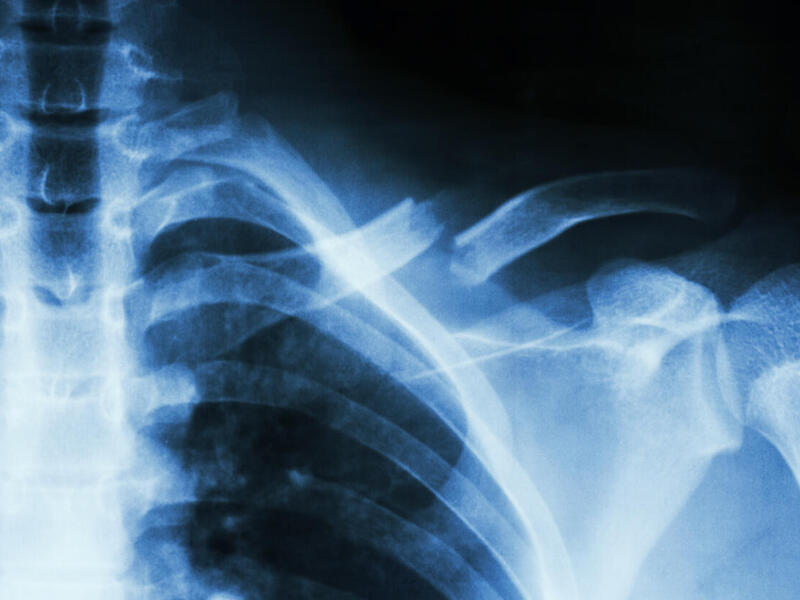

Individuals with spinal cord injury and resulting lower limb paralysis can retain some independence by using manual wheelchairs, but up to 84 percent of patients who use them develop shoulder pain associated with overuse injuries.

Peterson is researching how to improve health and quality of life for individuals with spinal cord injury who use manual wheelchairs — from childhood through adulthood. She is part of a team led by researchers at the University of Wisconsin-Milwaukee that has received a $2.5 million grant from the Eunice Kennedy Shriver National Institute of Child Health and Human Development at the National Institutes of Health. The four-year study is aimed at disease prevention for individuals with spinal cord injury through the use of advanced biomechanical modeling and diagnostic imaging.

Peterson, who will receive $413,544 under the grant, will generate computational simulations of musculoskeletal dynamics during wheelchair propulsion to quantify shoulder joint contact forces.